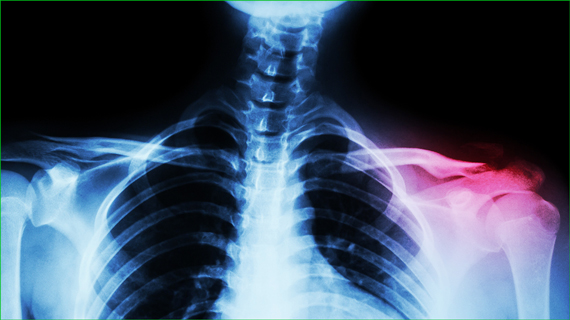

レントゲン検査で筋肉・腱・靭帯などは映りません。

靭帯は動かしてみなければ、どれくらい傷んでいるのか把握できません。

MRIでも把握出来ない場合があります。

当院では最新式の日立のエコー検査機があり、痛むところの正確な確認ができます。

レントゲン検査・CT・MRI などご希望の方はお気軽にお申し付けください。